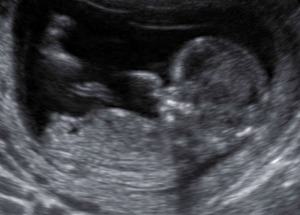

I was 13 weeks 5 days when these shots were taken. Would love your guesses whether you think it looks boy or girl! Thanks in advance! :)

nub and spine are parallel.